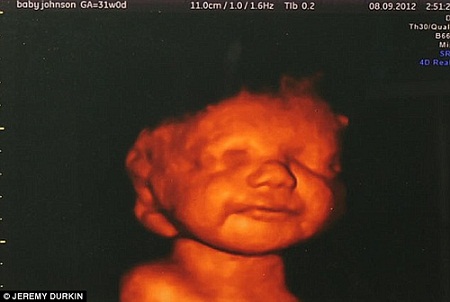

1月16日电 据外媒报道,英国26岁准妈妈卡提亚怀孕20周时,医生发现其胎儿脑部发育不良,并称胎儿出生后可能无法说话或走路,建议其堕胎。不过当卡提亚在三维扫描中看到胎儿的微笑后,毅然决定将孩子生下。虽然最终婴儿在出生9小时后便夭折,但卡提亚称她绝不后悔。

但当医生为胎儿进行详细的三维扫描时,卡提亚从屏幕中看到胎儿不时“微笑”,还在其腹中摆动手脚,展现了极强的生命力。她认为,胎儿的残障不阻碍他享受生命,因此决定不论儿子出生后命运如何,都不会剥夺他生存的权利。